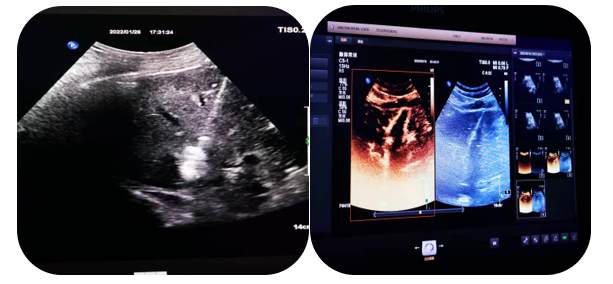

4.超聲介導(dǎo)下肝占位射頻及微波消融術(shù)

通過射頻電極發(fā)出高頻率射頻電流,電能使局部組織發(fā)生正負(fù)離子震蕩,并摩擦生熱達(dá)100°左右,熱能逐漸傳導(dǎo)至周圍組織,形成一個(gè)預(yù)定的球形或類球形的消融區(qū),腫瘤局部因高溫而發(fā)生凝固壞死。以達(dá)到和手術(shù)切除同樣的目的和效果。

5.超聲介導(dǎo)下囊腫硬化治療

局部麻醉患者清醒狀態(tài)超聲直視下穿刺針進(jìn)入囊腫囊腔內(nèi)抽出囊液,注入硬化劑,手術(shù)時(shí)間短,損傷輕微,痛苦小,安全性高。